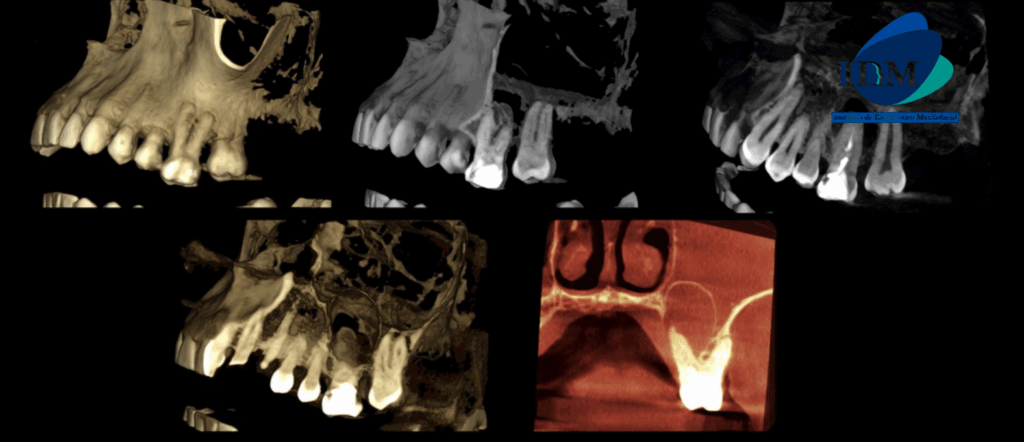

A la evaluación de la tomografía computarizada en cortes axiales, transaxiales y tangenciales se observa la pieza 16 con la raíz mesiovestibular con una obturación parcial y sobre extendida del conducto, asimismo presenta un conducto colateral obliterado y un proceso osteolítico periapical y reabsorción radicular externa del tercio apical; la raíz distovestibular presenta también una obturación parcial de conducto y la raíz palatina presenta un espigo intrarradicular, obturación parcial y subextendida del conducto y una imagen hipodensa corticalizada que desplaza hacia cefálico el piso de seno maxilar y compromete la tabla ósea palatina compatible con quiste radicular, asimismo ocasiona un engrosamiento de la mucosa antral ipsilateral compatible con sinusitis de origen odontogénico.

RECONSTRUCCIÓN 3D